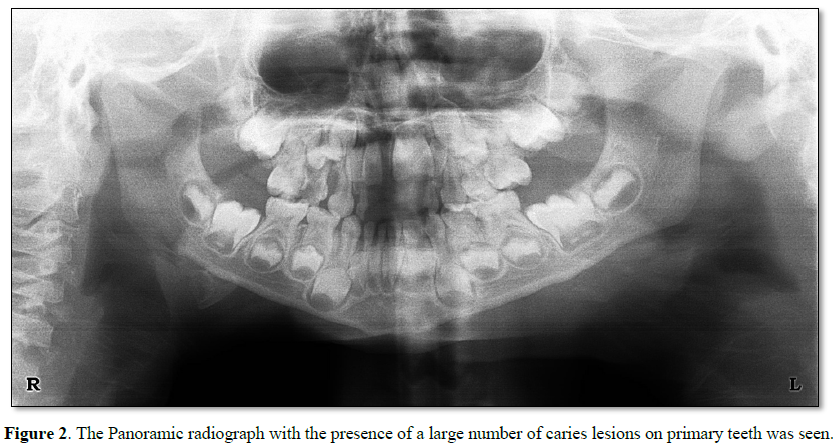

At the Department for Dental and Preventive Dentistry, a 5 year old male child (Figure 1) was referred by pediatric doctor for oral examination whether some carious teeth can be dental focus. The presence of a many carious teeth was largely confirmed on the orthopantomography (Figure 2). From an anamnesis that I took from the child's mother that the cyst was infected several time in the last six months. Also we received the information that the amoxicillin was prescribed by family doctor. During the first dental visit, extraction was carried out of the left primary incisor and the process of dental restoration started on all decay primary teeth. In the worst situation was the first right primary molar, with progressive caries lesion involving the pulp and periodontal space around the apex.